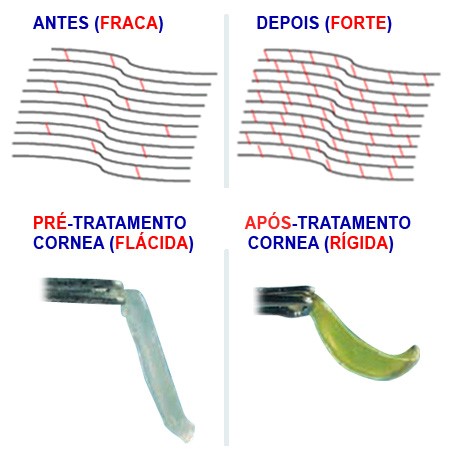

O procedimento “Cross-link ou Corneal Cross-Linking” consiste no uso de radiação ultravioleta, associada a uma substância chamada riboflavina, aumentando a rigidez biomecânica da Córnea. No Crosslinking ocorre o fortalecimento das fibras de colágeno, que representam as pontes de sustentação da Córnea. Com o aumento da resistência, diminui-se a elasticidade da córnea, reduzindo a chance de a progressão do Ceratocone.

O Crosslink diminui os processos inflamatórios de afinamento da Córnea e reduz a possibilidade de piora da doença a longo prazo. Um aspecto a ser destacado é que o CrossLink não é indicado aos pacientes com córneas muito finas ou com cicatrizes. Os resultados de estabilização do Ceratocone, com consequente melhora da acuidade visual, também dependem de acompanhamento clínico.

A Córnea, através Cross Link, tem sua resistência e rigidez aumentada tão logo termina a aplicação da luz ultravioleta e esta resistência se acentua ainda por alguns dias após o término do procedimento. Após 3 meses ao procedimento já se considera que a córnea está em formato e com rigidez pretendida, e como resultado final a progressão do Ceratocone ou a evolução da ectasia de córnea é interrompida.

Os estudos científicos demostram que o aumento na rigidez da Córnea possa ser de até 329%.